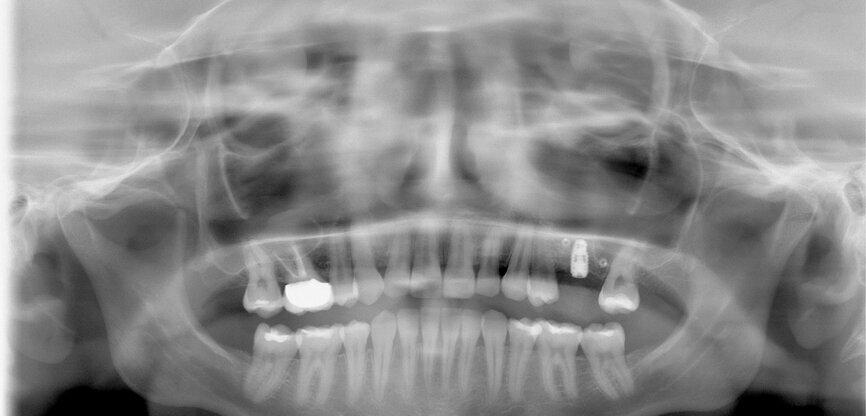

Fig. 11: Post-op dental panoramic tomogram.

The first was a 51-year-old patient who smoked 30 cigarettes per day and suffered from diabetes and stress (Figs. 1–8). The second was a 76-year-old male patient in good physical condition who smoked 40 cigarettes per day. He underwent reconstruction of the premaxilla (Figs. 9–13). The third was a healthy female patient of 24 years of age who smoked 20 cigarettes per day. She required a sinus lift in region #25 (Figs. 14–21). The patients were informed of the intended process in detail and signed the surgical protocol containing information concerning possible risks of failure and complications, as well as information on the alloplastic and synthetic materials to be used.

Digital radiographic images were taken at the time of surgery, 24 hours postoperatively and one month later in order to evaluate implant success (Figs. 6, 7, 11, 13, 15 & 20). In none of the patients inflammatory processes were found and all implants remained stable.